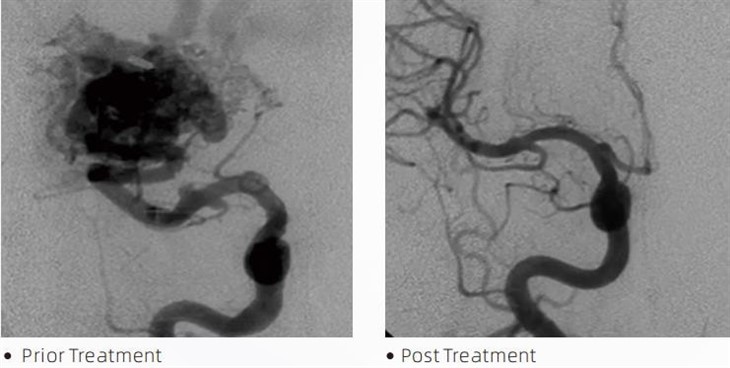

LavăTMAdezivul embolic este un dispozitiv medical utilizat de neuroradiologi intervenționali în timpul procedurilor minim invazive pentru a trata afecțiuni precum anevrismele cerebrale, malformațiile arteriovenoase și tumorile. Adezivul embolic Lava oferă multiple beneficii profesioniștilor din domeniul medical și pacienților deopotrivă în ceea ce privește siguranța, ușurința de utilizare și eficacitatea. Lava este capabilă să sigileze rapid și eficient vasele de sânge. Procesul implică injectarea adezivului direct în vasul vizat, unde se polimerizează și se întărește într-o masă asemănătoare turnării care umple anevrismul sau malformația. Apoi, întrerupe eficient fluxul de sânge către leziune, prevenind ruperea acesteia și reducând riscul de deteriorare permanentă sau accident vascular cerebral. Lava include Lava-12, Lava-18 și Lava-34. Fiecare formulă este concepută pentru a răspunde nevoilor clinice specifice. Lava-18 este o formulare standard pentru uz general. Lava-34 este un adeziv cu vâscozitate ridicată pentru vase cu debit mare. În timp ce Lava-12 are o vâscozitate mai mică și este mai fluidă, permițând microvasele distale. Cu aceste opțiuni, neuroradiologii intervenționali pot alege formulările Lava potrivite pentru a asigura rezultate optime. Una dintre cele mai remarcabile caracteristici ale Lavei este proprietățile sale neadezive. Această substanță este special formulată pentru a rămâne stabilă până când ajunge în zona vizată. Această caracteristică înseamnă că lipiciul embolic Lava poate fi plasat cu precizie în arteră și să rămână acolo fără să se lipească sau să se lipească de țesutul din jur.